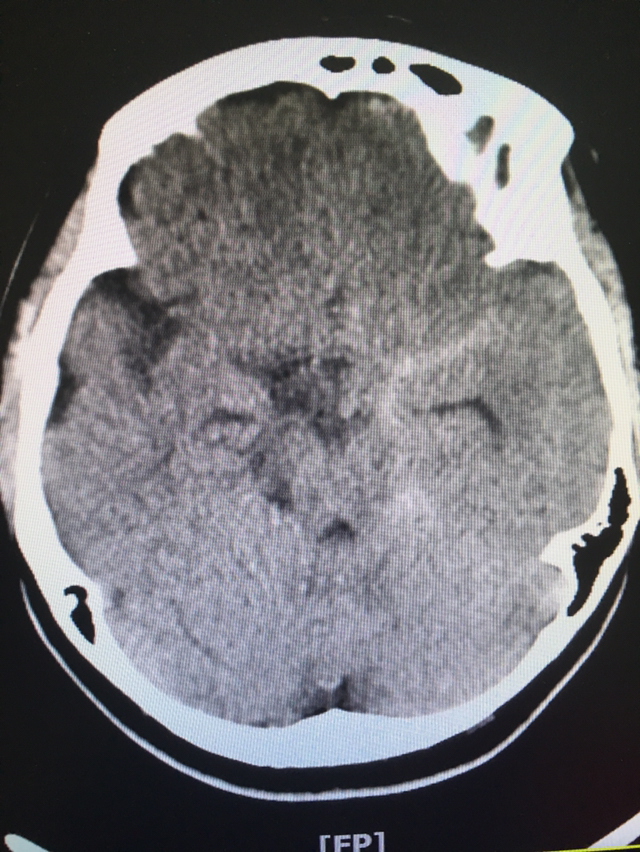

역시나 출혈

지주막하출혈 CT

극심한 두통을 호소해

신경외과로 입원시킨 여인의 CT다.

미심쩍었던 부위가

지주막하출혈로 확인됐다.